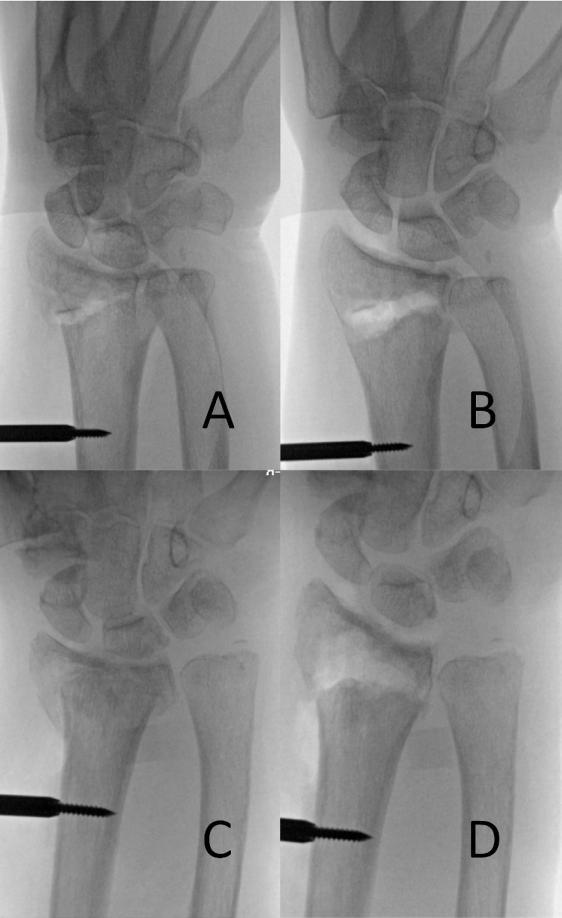

随后,通过将腕部抬离床面20°获取桡偏角侧位影像。利用迷你牵引器作为手柄可稳定获取正交位影像,避免复位丢失(图4A)。仅靠牵引器常无法完全恢复掌倾角。在牵引器固定桡骨高度和桡偏角后,可通过钢板可靠恢复掌倾角。作者推荐两种恢复掌倾角的技术:一种先将钢板固定于骨干,再以钢板为模板复位骨折;另一种先将钢板固定于远端骨折块,再用Verbrugge钳将钢板复位至骨干(图3)。迷你牵引器通过临时稳定冠状面复位,使术者可专注于恢复矢状面对位。所有内固定置入后,需通过Hoya位确认螺钉未穿透背侧皮质。Hoya位拍摄方法为:屈肘90°、屈腕、肩关节外旋20°,X线沿腕背侧投射。若发现过长螺钉需更换(图4B)。

图3. 使用掌侧钢板作为复位模板恢复掌倾角(A、B);通过将钢板固定于远端骨折块(C),并用Verbrugge钳复位至骨干(D)。